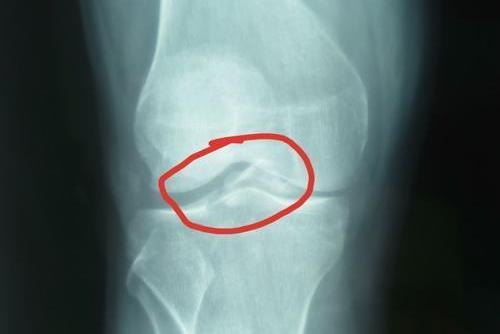

胫骨髁间嵴撕脱性骨折

表现为膝关节疼痛、肿胀、无法负重、屈伸活动受限。体格检查时可见膝关节肿胀、前后方稳定性降低,前抽屉试验和Lachman试验可为阳性。X线片可清楚显示髁间嵴骨折和移位。